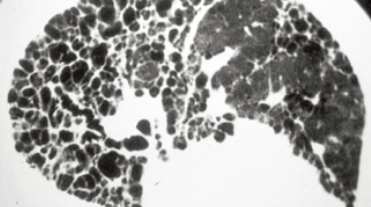

폐섬유증은 폐 조직이 점차 굳어지면서 호흡장애를 일으키는 질환인데요. 폐섬유화증은 폐섬유증의 한 종류로, 폐 조직이 딱딱해지는 현상을 의미합니다. 이러한 변화는 폐에 염증이 생겼다가 아무는 것이 반복되면서 마치 상처가 굳은살과 흉터를 만드는 것과 비슷한데요.

폐섬유증과 폐섬유화증의 주요 원인은 다양합니다. 그러나 가장 흔한 원인 중 하나는 만성 염증입니다. 만성 염증은 폐 조직에 지속적인 염증 반응을 유발하며, 이는 폐 조직의 손상과 염증 반응이 반복되면서 섬유화 과정을 유발합니다. 이 과정에서 폐 조직 내 결합조직이 비정상적으로 증식하고 딱딱하게 굳어지는 현상이 나타나게 됩니다.